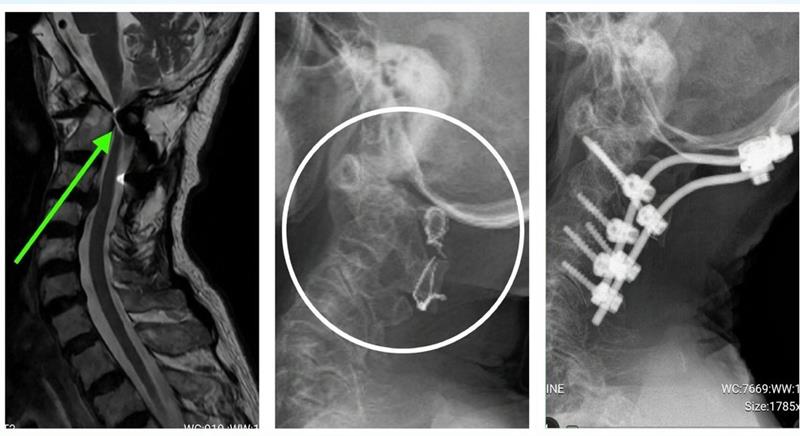

Phim chụp cho thấy tổn thương đốt sống cổ cao của bệnh nhân

ThS-BS Nguyễn Xuân Hùng, chuyên khoa ngoại thần kinh cho biết, đây là ca mổ khó, có mức độ rủi ro cao. Tủy cổ cao có nguy cơ bị tổn thương khi phẫu thuật do đã bị chèn ép quá nặng. Nếu tủy bị tổn thương, nguy cơ liệt tứ chi, thậm chí tử vong là rất lớn.

Gãy đốt sống cổ cao là bệnh lý hiếm gặp, bởi đa phần bệnh nhân bị gãy vùng này nếu có tổn thương tủy nặng thì đã tử vong ngay. Số còn lại sống sót, chỉ có triệu chứng nổi bật là đau cột sống cổ ở vùng bị gãy. Khi đã xuất hiện tê, yếu tứ chi tức là tủy cổ đã bị chèn ép nặng. Nếu không phát hiện và điều trị, sẽ di lệch tiến triển gây chèn ép tủy, sau đó yếu và liệt tứ chi.

1 tuần sau phẫu thuật, bệnh nhân đã hết tê bì chân tay, sức cơ tứ chi cải thiện nhiều, có thể đi được với khung nạng tập đi.